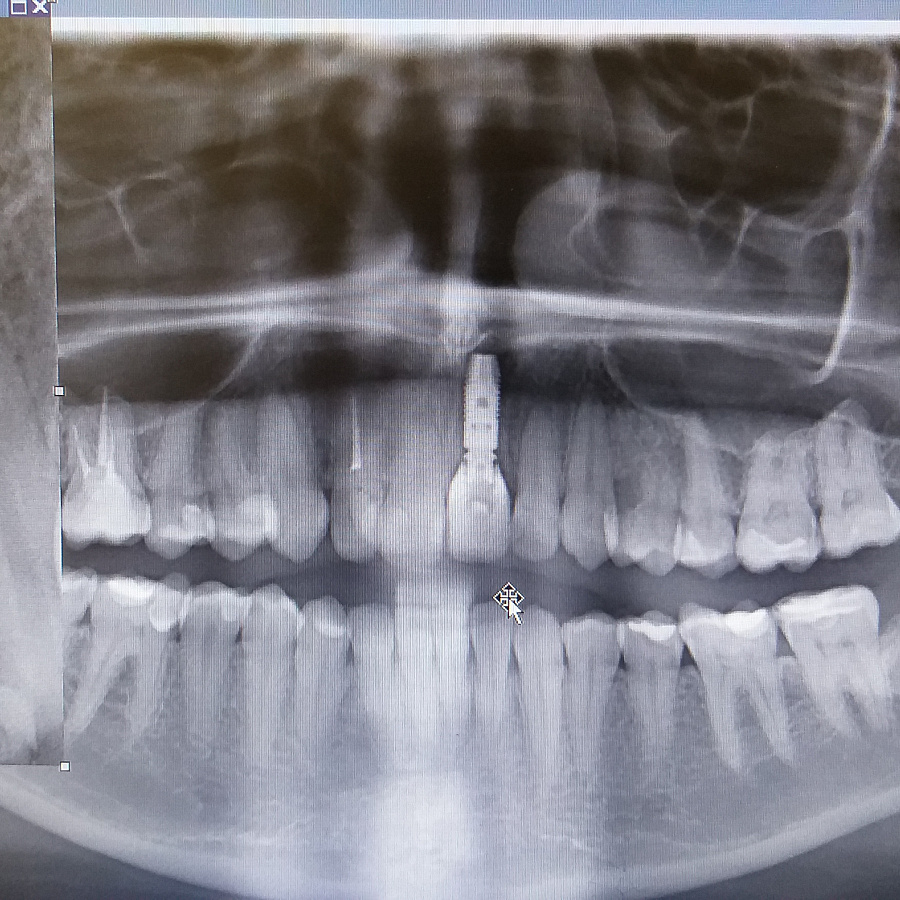

Пациентка обратилась в клинику с жалобами на воспаление десны в области переднего зуба верхней челюсти, необычный вид десны, кровоточивость десны во время чистки зубов.

Поставлен диагноз посттравматическая резорбция корня.

Был предложен вариант одномоментной имплантации (удаление зуба и установка импланта за одно посещение).

Следующий этап после удаления разрушенного корня и установки зубного имплантата - восстановление косметического дефекта временной коронкой, изготовленной после операции.